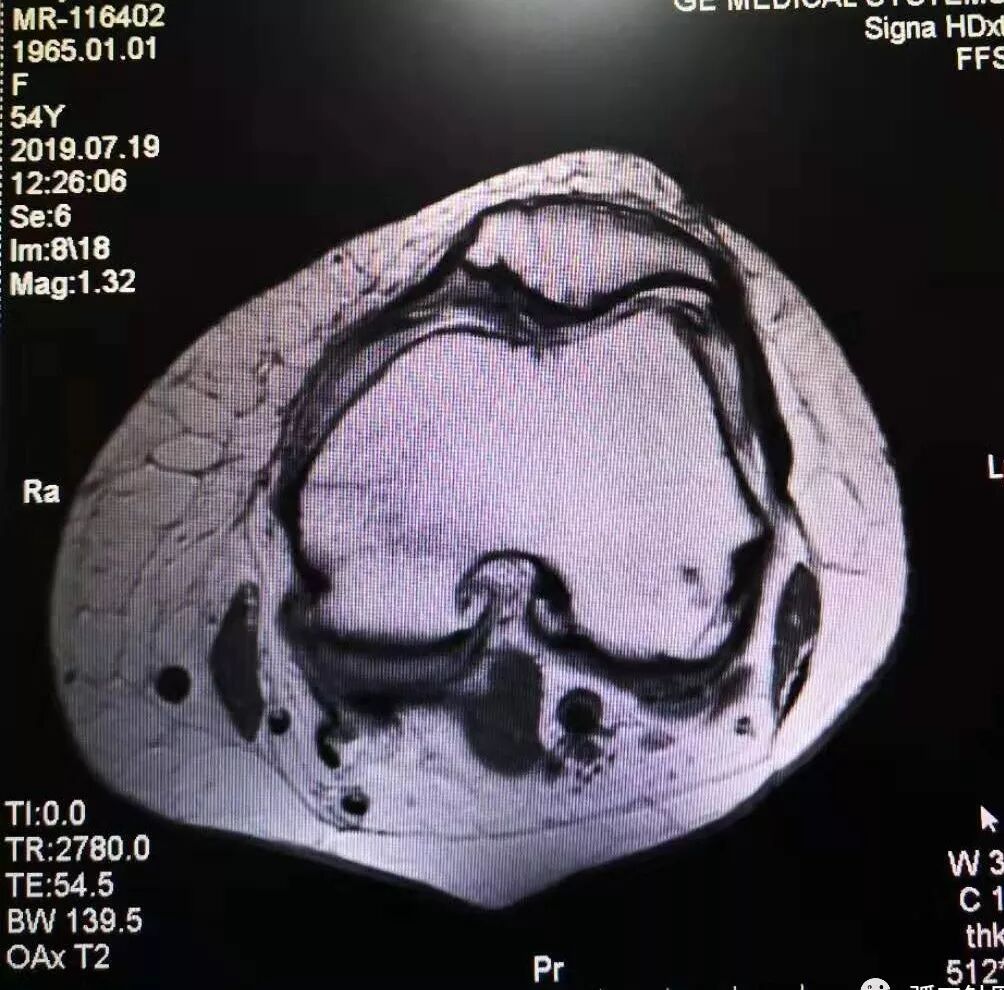

膝关节骨关节炎的磁共振影像

一例弧刃针标准疗法治膝关节骨关节炎的典型病例